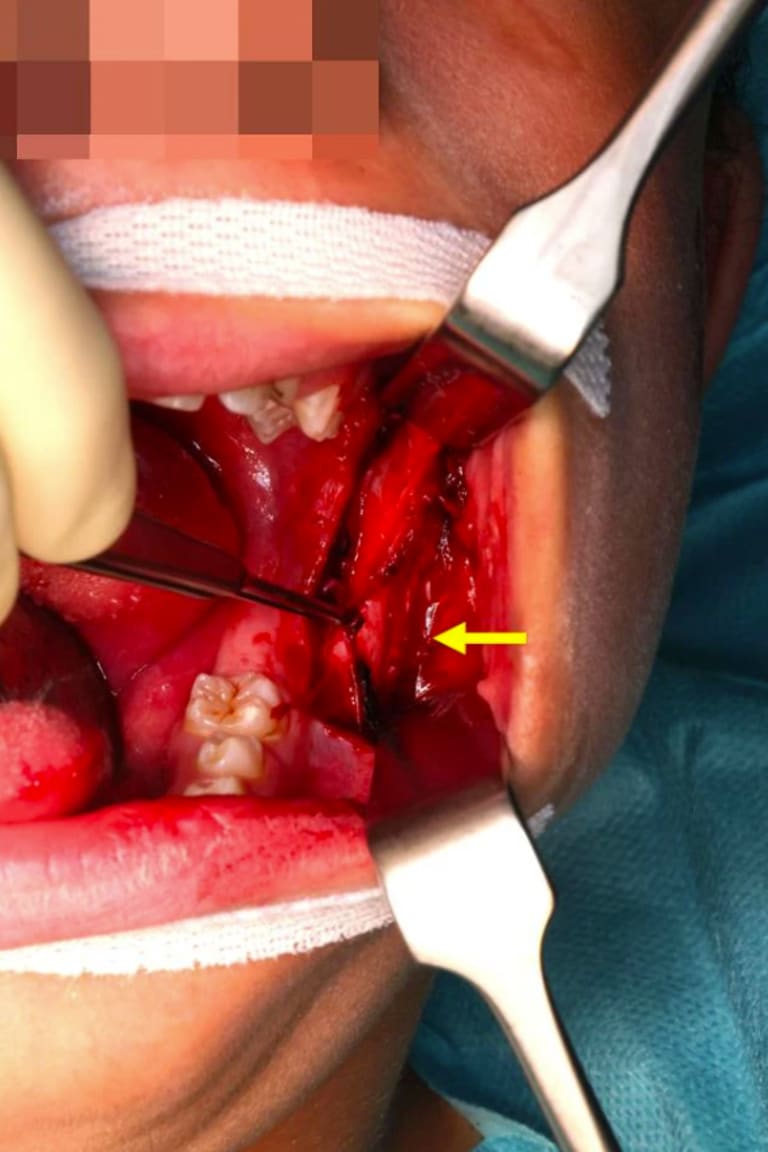

Abb. 4: Operationssitus: supraperiostale Präparation der intramuskulären Raumforderung (Pfeil).